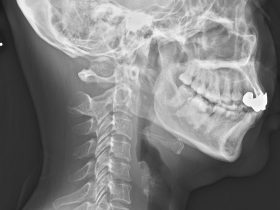

ストレートネックが治らない原因と診断及び治し方

「ストレートネックが治らない原因と診断及び治し方」 ストレートネックとは 首の正常な曲線は、通常レントゲン写真の側面から見た時、17㎝の半円を描いた前彎の曲線の位置になければなりません。 主な原因には、長時間の…